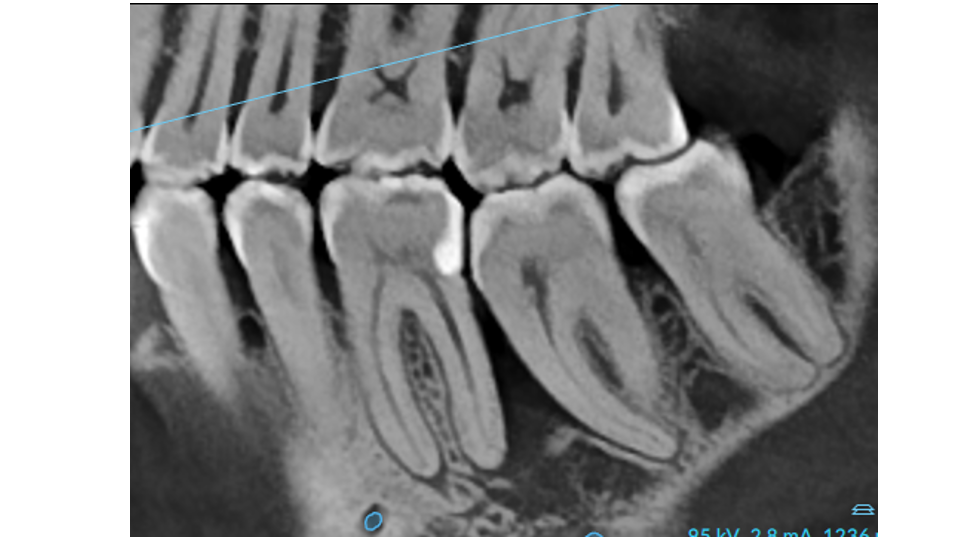

- Local anatomy – Tooth position, bone thickness, and furcations affect how the disease progresses

In deeper pockets (6 mm or greater), reaching every surface becomes increasingly difficult due to limited access and complex root anatomy. This is one of the reasons deeper sites sometimes need surgical treatment after healing, so we can gain the direct visibility that closed instrumentation cannot provide.

- Starting pockets of 6 mm or deeper: Deep cleaning typically achieves 2 to 3 mm of reduction, but pockets often remain at 4 to 6 mm or deeper. When this happens, surgical treatment is usually needed to fully address the remaining disease.

- Pockets at 6 mm or deeper: These sites have craters in the bone that are preventing complete healing. Surgery is needed to access these areas and correct the bone architecture.